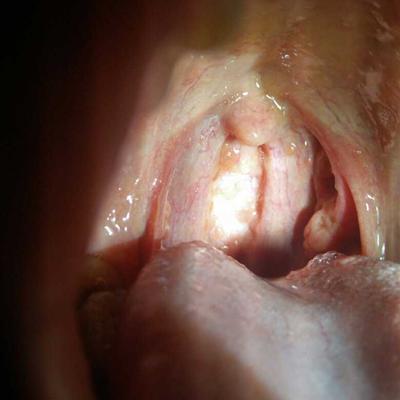

The coating on the tongue is thick and sometimes white, especially when you are hungry. The coating on the tongue near the base of the tongue is dry and split into small pieces. It started in July and August last year. Sometimes the surface of the tongue is very rough and the tongue is very white. They all say that the head of the tongue can reflect a person's disease, So what's the matter with thick and white tongue coating? Let's talk about it now.

Second, different tongue coating symptoms reflect different gastrointestinal diseases. Moss can be seen in addition to the normal disease-free people, more common in mild disease or disease recovery period. Tongue coating is white, thick and dry, which indicates that gastrointestinal lesions have occurred, patients may suffer from gastritis and other stomach diseases, so we still need to go to the hospital to do a detailed examination, do not blindly use drugs, also can not miss the best treatment time.

Third: thick and white tongue coating is a warning of gastrointestinal metaplasia, so we must pay attention to it when it is thick and white, otherwise it may cause more serious diseases. Thick and white tongue coating is only a symptom, which is closely related to stomach fire in traditional Chinese medicine. Can drink Chinese medicine to regulate the body, must be timely treatment, otherwise it will cause more serious disease.